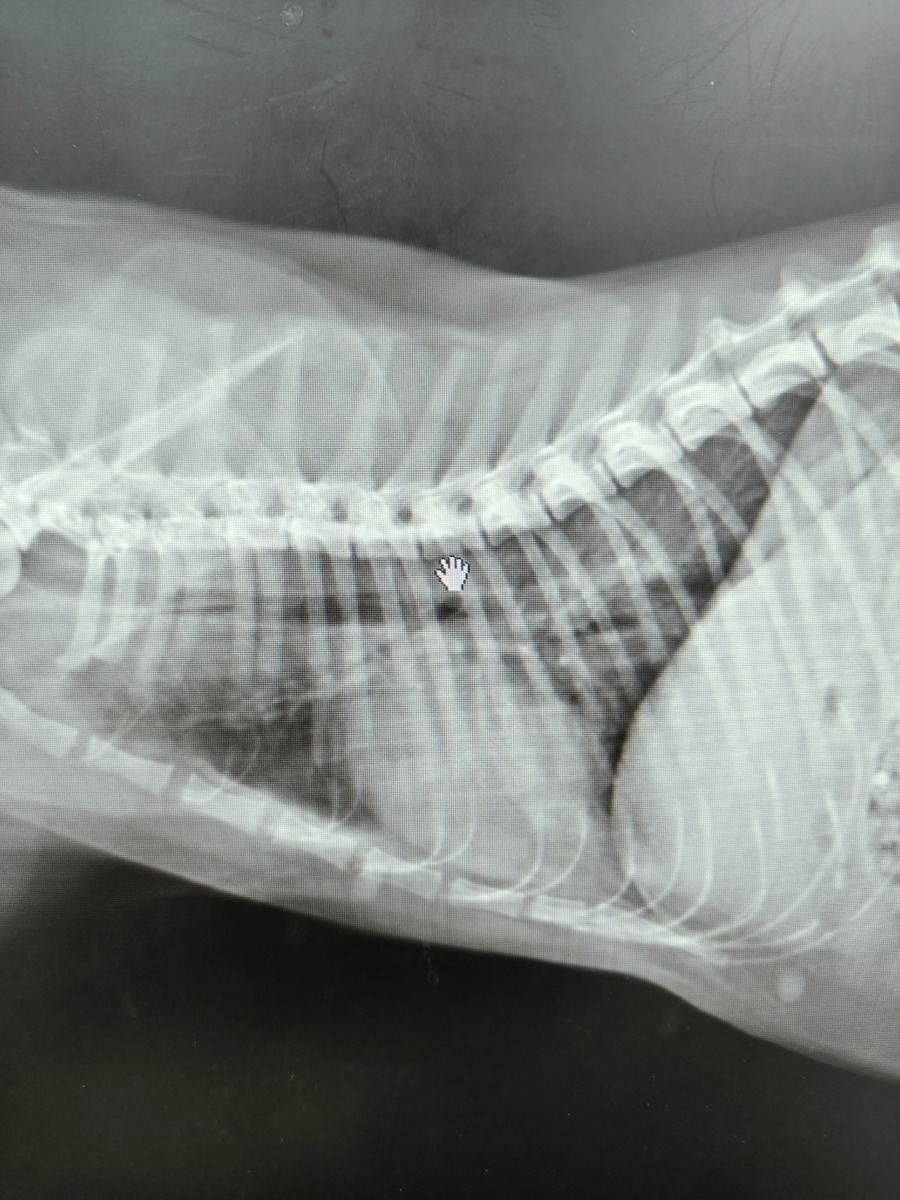

Как рассказала редакции SmolNarod Виктория, пуля была обнаружена в теле животного случайно, в ходе планового осмотра перед кастрацией. Прежде чем попасть к нынешней хозяйке, кот жил на улице, поэтому определить, когда и тем более кто совершил выстрел, не представляется возможным. Благо, снаряд застрял под кожей хвостатой жертвы, не причинив значительных повреждений.

«Спасать его не пришлось, пуля просто находилась под кожей и не причиняла коту дискомфорта на момент приема. Рана после выстрела зажила самостоятельно и наружных травм обнаружено не было. Мы извлекли пулю планово одновременно с проведением кастрации», — поделилась ветеринарный врач.